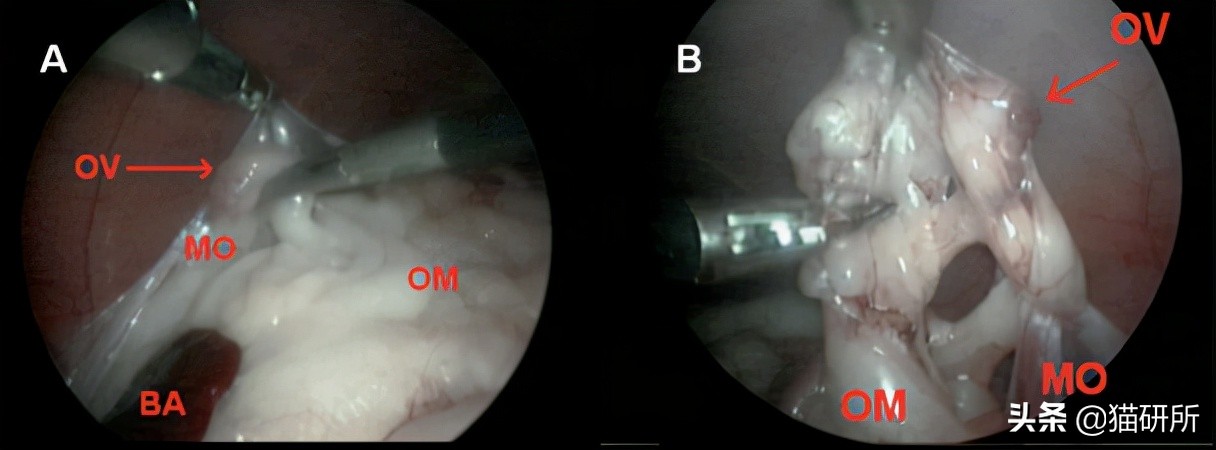

OV为残留的卵巢组织,粘附在左侧系膜(MO)和网膜(OM)上

图自:researchgate